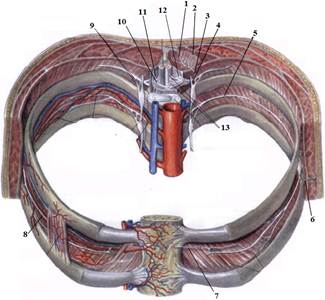

1. Яким номером позначено N. thoracicus?

2. Яким номером позначено N. intercostalis?

3. Яким номером позначено R. cutaneus lateralis?

4. Яким номером позначено R. dorsalis n. thoracici?

5. Яким номером позначено R. cutaneus lateralis r.dorsalis n. thoracici?

6. Яким номером позначено R. cutaneus medialis r.dorsalis n. thoracici?

7. Яким номером позначено R. cutaneus anterior?

8. Яким номером позначено Rr.communicantes n. thoracici?

9. Яким номером позначено Radix dorsalis n. thoracici?

10. Яким номером позначено Radix ventralis n. thoracici?